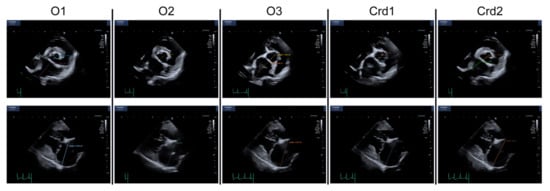

| O1 | O2 | O3 | Crd1 | Crd2 | |